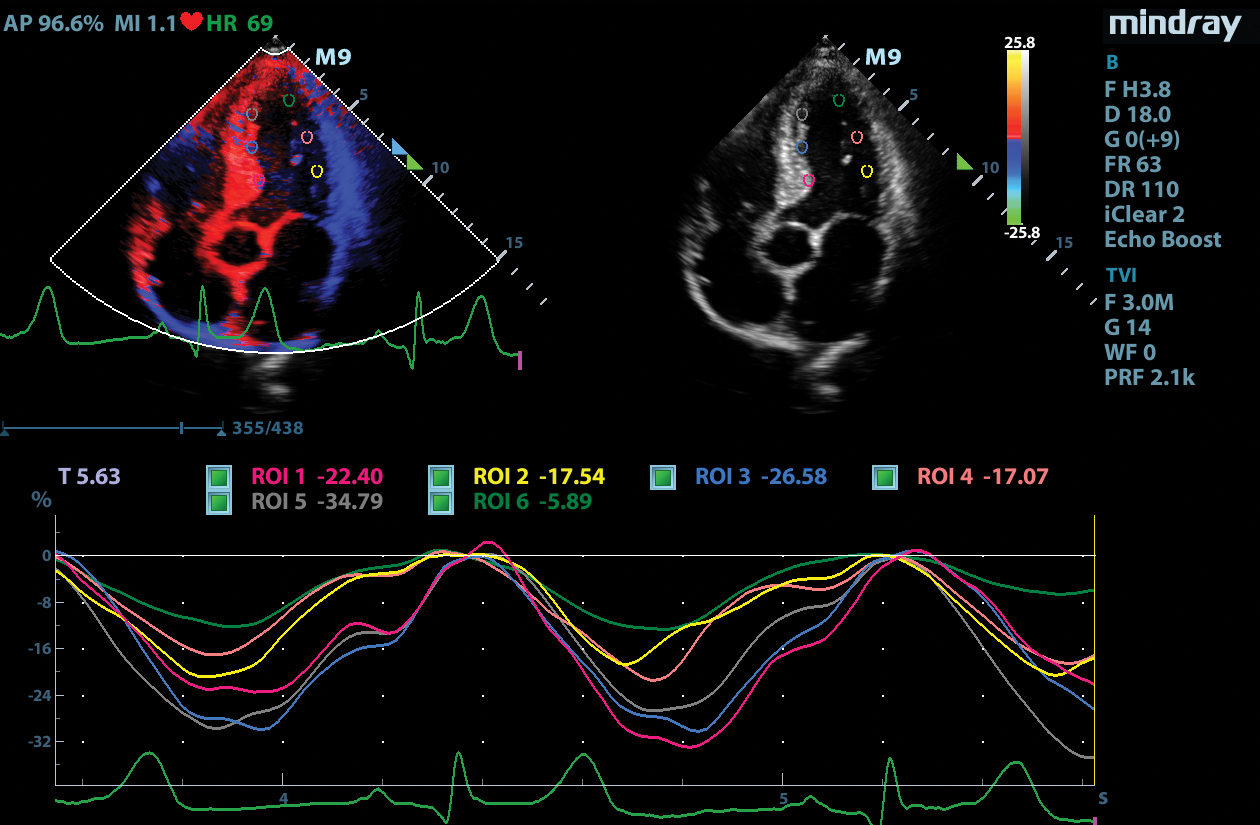

Tissue Tracking

Mindray’s Tissue Tracking technology with quantitative analysis allows users to monitor the displacement of cardiac tissue by tracking the speckle displacement in the image from frame to frame. This non-angle dependent tool with onboard analysis, can be performed at the bedside, saving time and simplifying challenging cases.